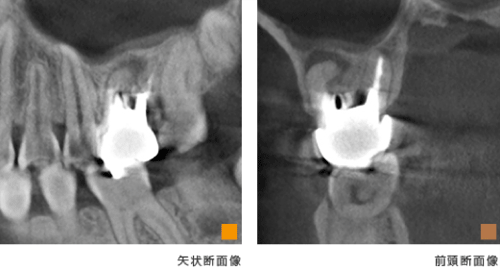

歯科用CT画像

インプラント治療とCT

インプラント治療では、術前の骨の状態(質や厚み、高さ、形態など)を正確に判断ができるので、切開や剥離をしない手術など に対して、すぐに判断が可能です。歯科用CTでの撮影画像をもとに、的確な治療計画を立てることは、安心・安全な治療への第一歩です。